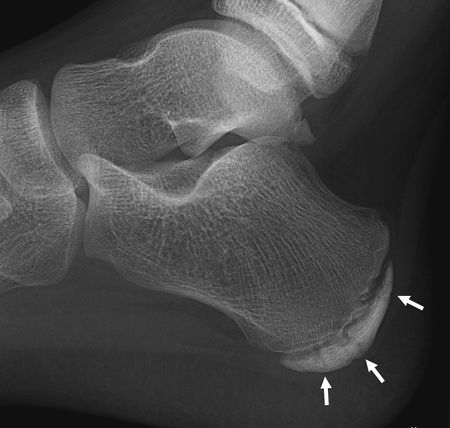

臨床上,醫護人員會檢查傷患的位置並作出一些特定的測試包括:觸診、關節活動幅度及肌肉柔軟度、擠壓測試(Squeeze Test)、足尖站立及步姿檢查等等從而作出準確的臨床診斷。X-光檢查可排除其他足跟痛的成因。

| X光下所見的跟骨生長板 | 小腿伸展運動 | |